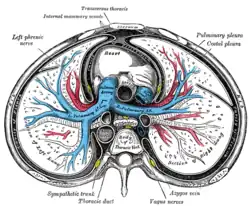

Inferior view of the human brain, with the cranial nerves labeled.

Inferior view of the human brain, with the cranial nerves labeled. -

Transverse section of thorax, showing relations of pulmonary artery

Transverse section of thorax, showing relations of pulmonary artery -